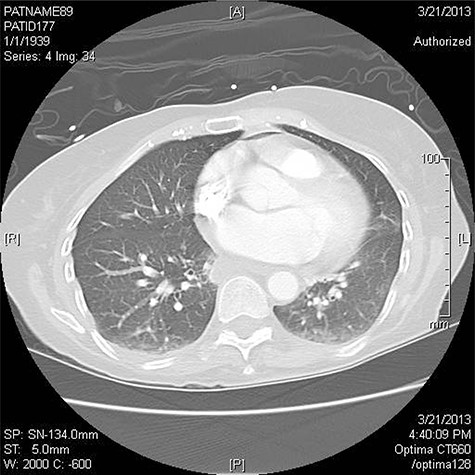

Three patients have been treated by a single surgeon for left AEF. All presented with similar symptoms: chest pain, fever and dysphagia. The diagnosis was confirmed on CT scan of the chest (Fig. 1).

CT chest is the confirmatory test of choice [1, 3, 6, 8]. Findings include pericardial effusion, intravascular air, communication between the atrium and the pericardium or esophagus, and extensive systemic emboli [3]. Pneumomediastinum is a strong indicator of esophageal injury [1]. For patients who have neurologic symptoms a CT head is recommended [1].